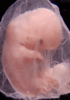

Carnegie Stage 19 (47 post-ovulatory days)

About Carnegie Stage 19

Most embryos at stage 19 are approximately 47-48 post-ovulatory days old and measure 17-20 mm in length. Distinguishing criteria for this stage include straightening of the trunk, the limbs extend nearly directly forward, toe rays are prominent, but interdigital notches have not yet appeared in the foot.

Although some of the photographs below show abnormal embryos, the animations and MRI slice images all depict normal embryos. Abnormal embryos are noted in the titles of the large photos when they are opened.